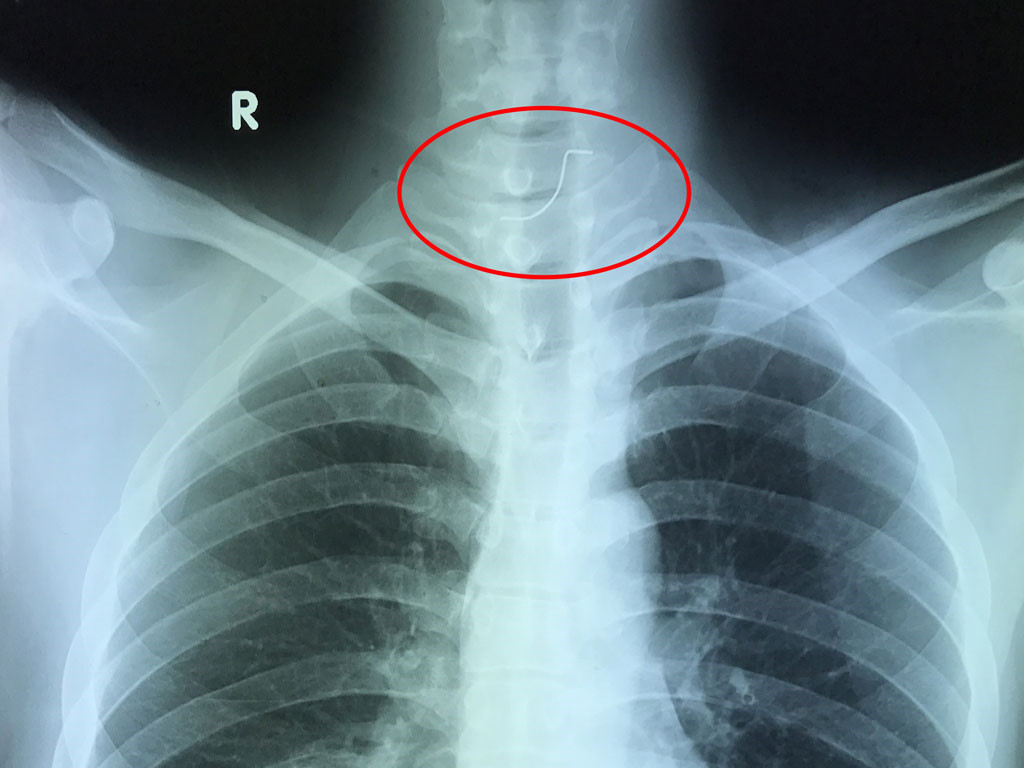

Chụp X-quang để phát hiện vết rách.

Click vào ảnh để xem 4 hình ảnh minh họa